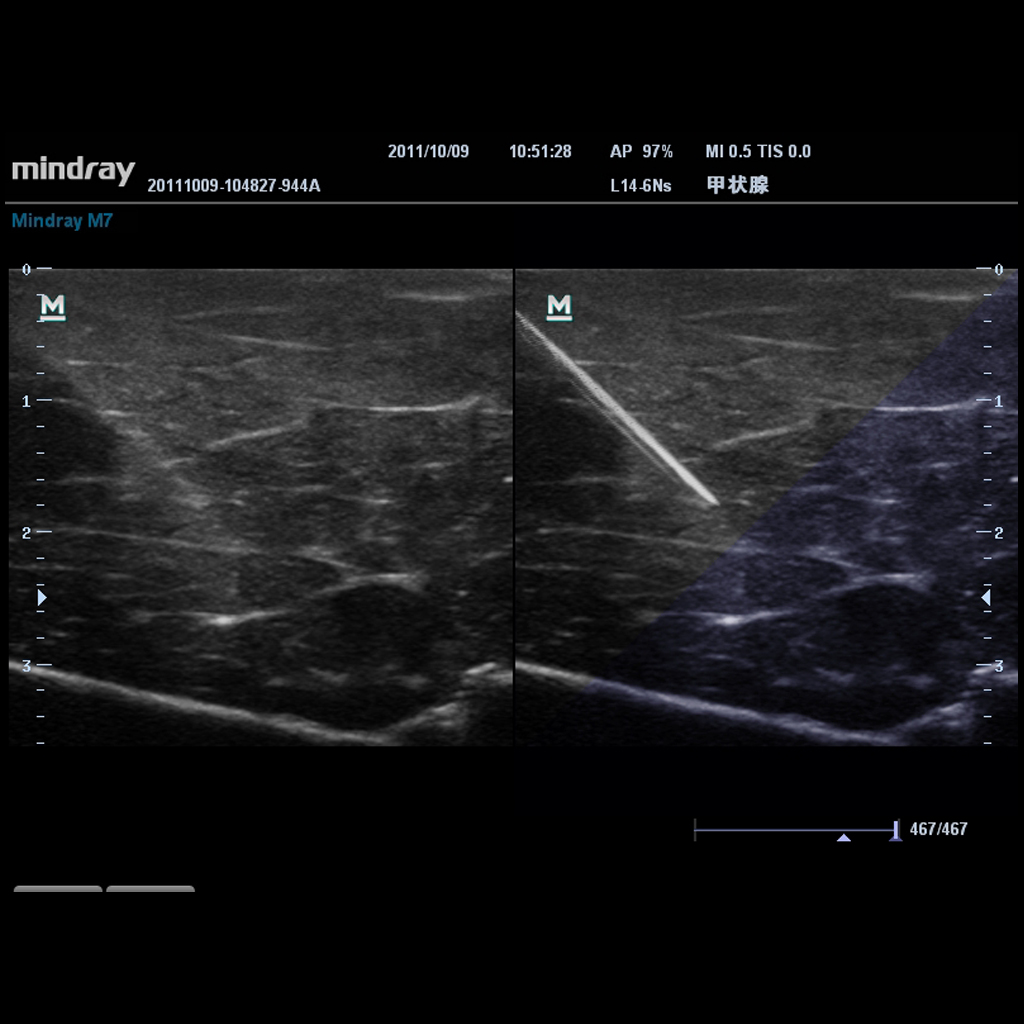

Режим на прецизно визуализиране на биопсионната игла. Изключително полезен особено при дълбока биопсия: позволява корекции на линията на сканиране, за да се постигне по-добра видимост както на иглата, така и на нервите и малките съдове и да се намали до минимум вероятността за увреждането на околните тъкани при манипулации.